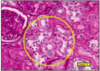

JUXTAGLOMERULAR APPARATUS (PAS)

- afferent/efferent arterioles, macula densa, lacis cells

- afferent - cells produce renin - granules in cytoplasm

- renin catalyses angiotensin 1 (liver) -> angiotensin 2 (conversion at lungs) -> aldosterone release by suprarenal cortex -> reabsorption of sodium and water @ distal tubules and collecting ducts

- lacis cells and macula densa regulate renin secretion by monitoring sodium levels

this slide - obvious macula densa